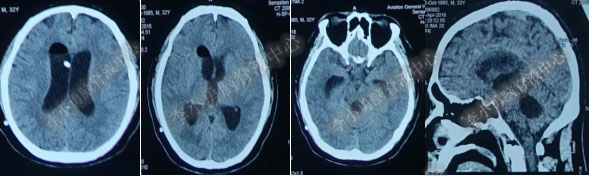

2016年5月9日因“间断性眩晕半月,恶心呕吐一周”以“梗阻性”脑积水,第1次住入北京某企业三级医院神经外科内镜组。2016年5月10日(入院后第2天)行头部MRI(图-1)检查示脑室系统扩张。

图-1:2016年5月10日头部MR

术后7天(2016年5月18日),症状有所缓解,复查头部MRI(图-2)幕上脑室较术前缩小,但是“四脑室仍扩张”,医生认为 “正常”于术后8天(2016年5月19日)出院。

图-2:2016年5月18日头部MRI